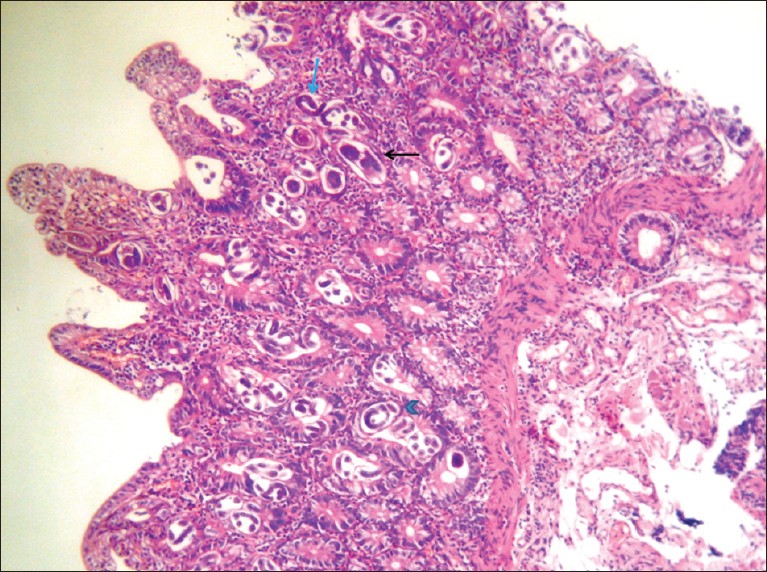

The formalin fixed, H and E stained sections of duodenal biopsies showed florid S. stercoralis infestation with eggs, both larval and adult forms of the parasite within the crypts of duodenal mucosa and even on the surface epithelium [Figure 1] and [Figure 2]. The lamina propria showed inflammatory infiltrates consisting of neutrophils, eosinophils, few lymphocytes and plasma cells. A histopathological diagnosis of Strongyloidiasis of duodenum was made. Subsequently stool examination was carried out which revealed heavy parasitization by S. stercoralis showing rhabditiform larvae having bulbous enlargement at esophageal end and slender tail end [Figure 3] and [Figure 4]. Patient was put on albendazole 400 mg twice daily for 14 days and recovered completely. On the 15 th day stool examination was done which did not reveal any parasite. His family members were also screened and no parasites were identified in the stool examination.

Figure 1: Photomicrograph of duodenal mucosa – eggs (black arrow), larval (blue arrow head) and adult forms (blue arrow) of Strongyloides stercoralis within the crypts and surface epithelium (H and E, ×100) |